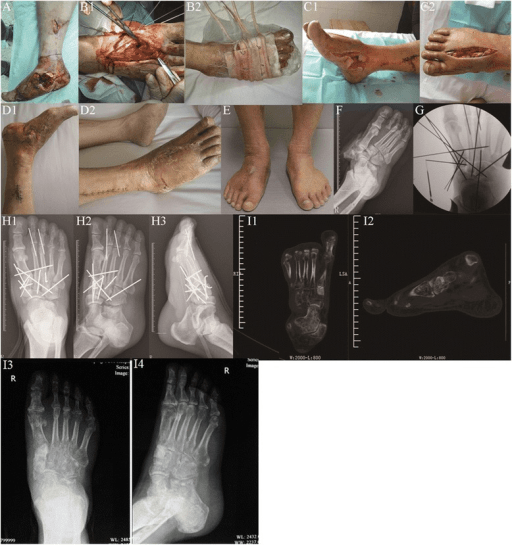

The practical scope remains foot-and-ankle dominant. The literature is strongest for syndesmosis assessment, adult-acquired flatfoot, cavovarus deformity, hallux valgus planning, ankle osteoarthritis, and post-operative reduction analysis. Outside those indications, WBCT is still emerging and should not be treated as a universal replacement for conventional CT.

Clinical Imaging

Imaging Gallery

Clinical Applications